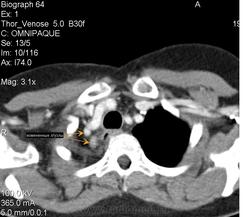

Случай 1. Пациент А. Женщина 52 года, после оперативного лечения (верхняя лобэктомия справа) 26.03.2009г. Гистологическое заключение: железисто-солидный вариант (низкодифференцированная аденокарцинома) с метастазами в бронхопульмональные лимфоузлы. Проведен послеоперационный курс дистанционной гамма-терапии, при контрольном ультразвуковом исследовании органов брюшной полости выявлено метастатическое поражение печени. Диагноз: немелкоклеточный рак правого легкого 4й стадии. На МР-томограммах определяются образования области верхушки правого легкого, корня правого легкого, печени. На КТ-томограммах определяются образования области верхушки правого легкого, утолщение плавры (исследование проведено через 7 месяцев после МРТ).

Вокруг правого главного бронха муфтообразное утолщение, кзади участок пневмонита, обтурация сегментаного бронха.